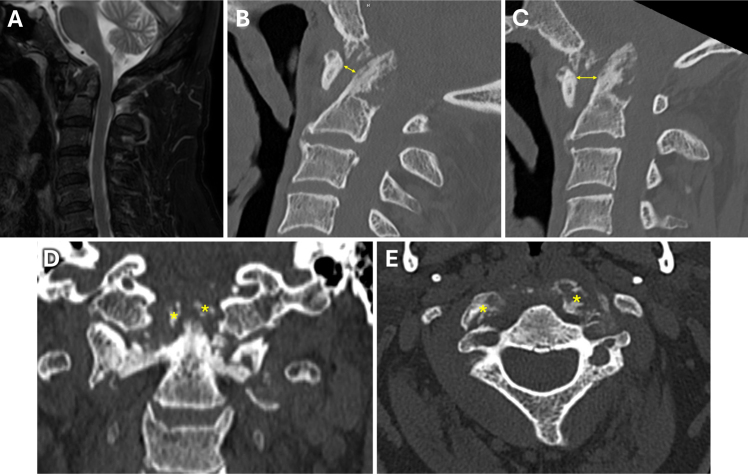

Observations: A 65-year-old male presented with worsening chronic cervicalgia, occipital headaches, and unstable tandem gait. CT revealed basilar impression with severe atlantoaxial erosion and instability, absent on imaging 8 months prior. MRI showed high-grade CCJ stenosis without myelopathy, due to CPPD. Before treatment could be initiated, the patient was suddenly found unresponsive. CT showed posterior fossa hemorrhage due to VA dissection, with secondary obstructive hydrocephalus. An external ventricular drain was placed, followed by coil VA embolization. After halo vest placement, CCJ alignment was restored and the patient underwent occipitocervical fusion. Following prolonged rehabilitation, he regained independent living without significant neurological sequelae.

Lessons: This is the first reported case of VA dissection with posterior fossa hemorrhage secondary to basilar impression due to CPPD. Inflammatory arthritides of the CCJ may cause rapidly progressive atlantoaxial erosion, predisposing one to unstable basilar impression and VA dissection. Awareness of this risk is crucial in the surgical management of inflammatory basilar impression, where preoperative vascular imaging may be warranted in selected cases. https://thejns.org/doi/10.3171/CASE25332.